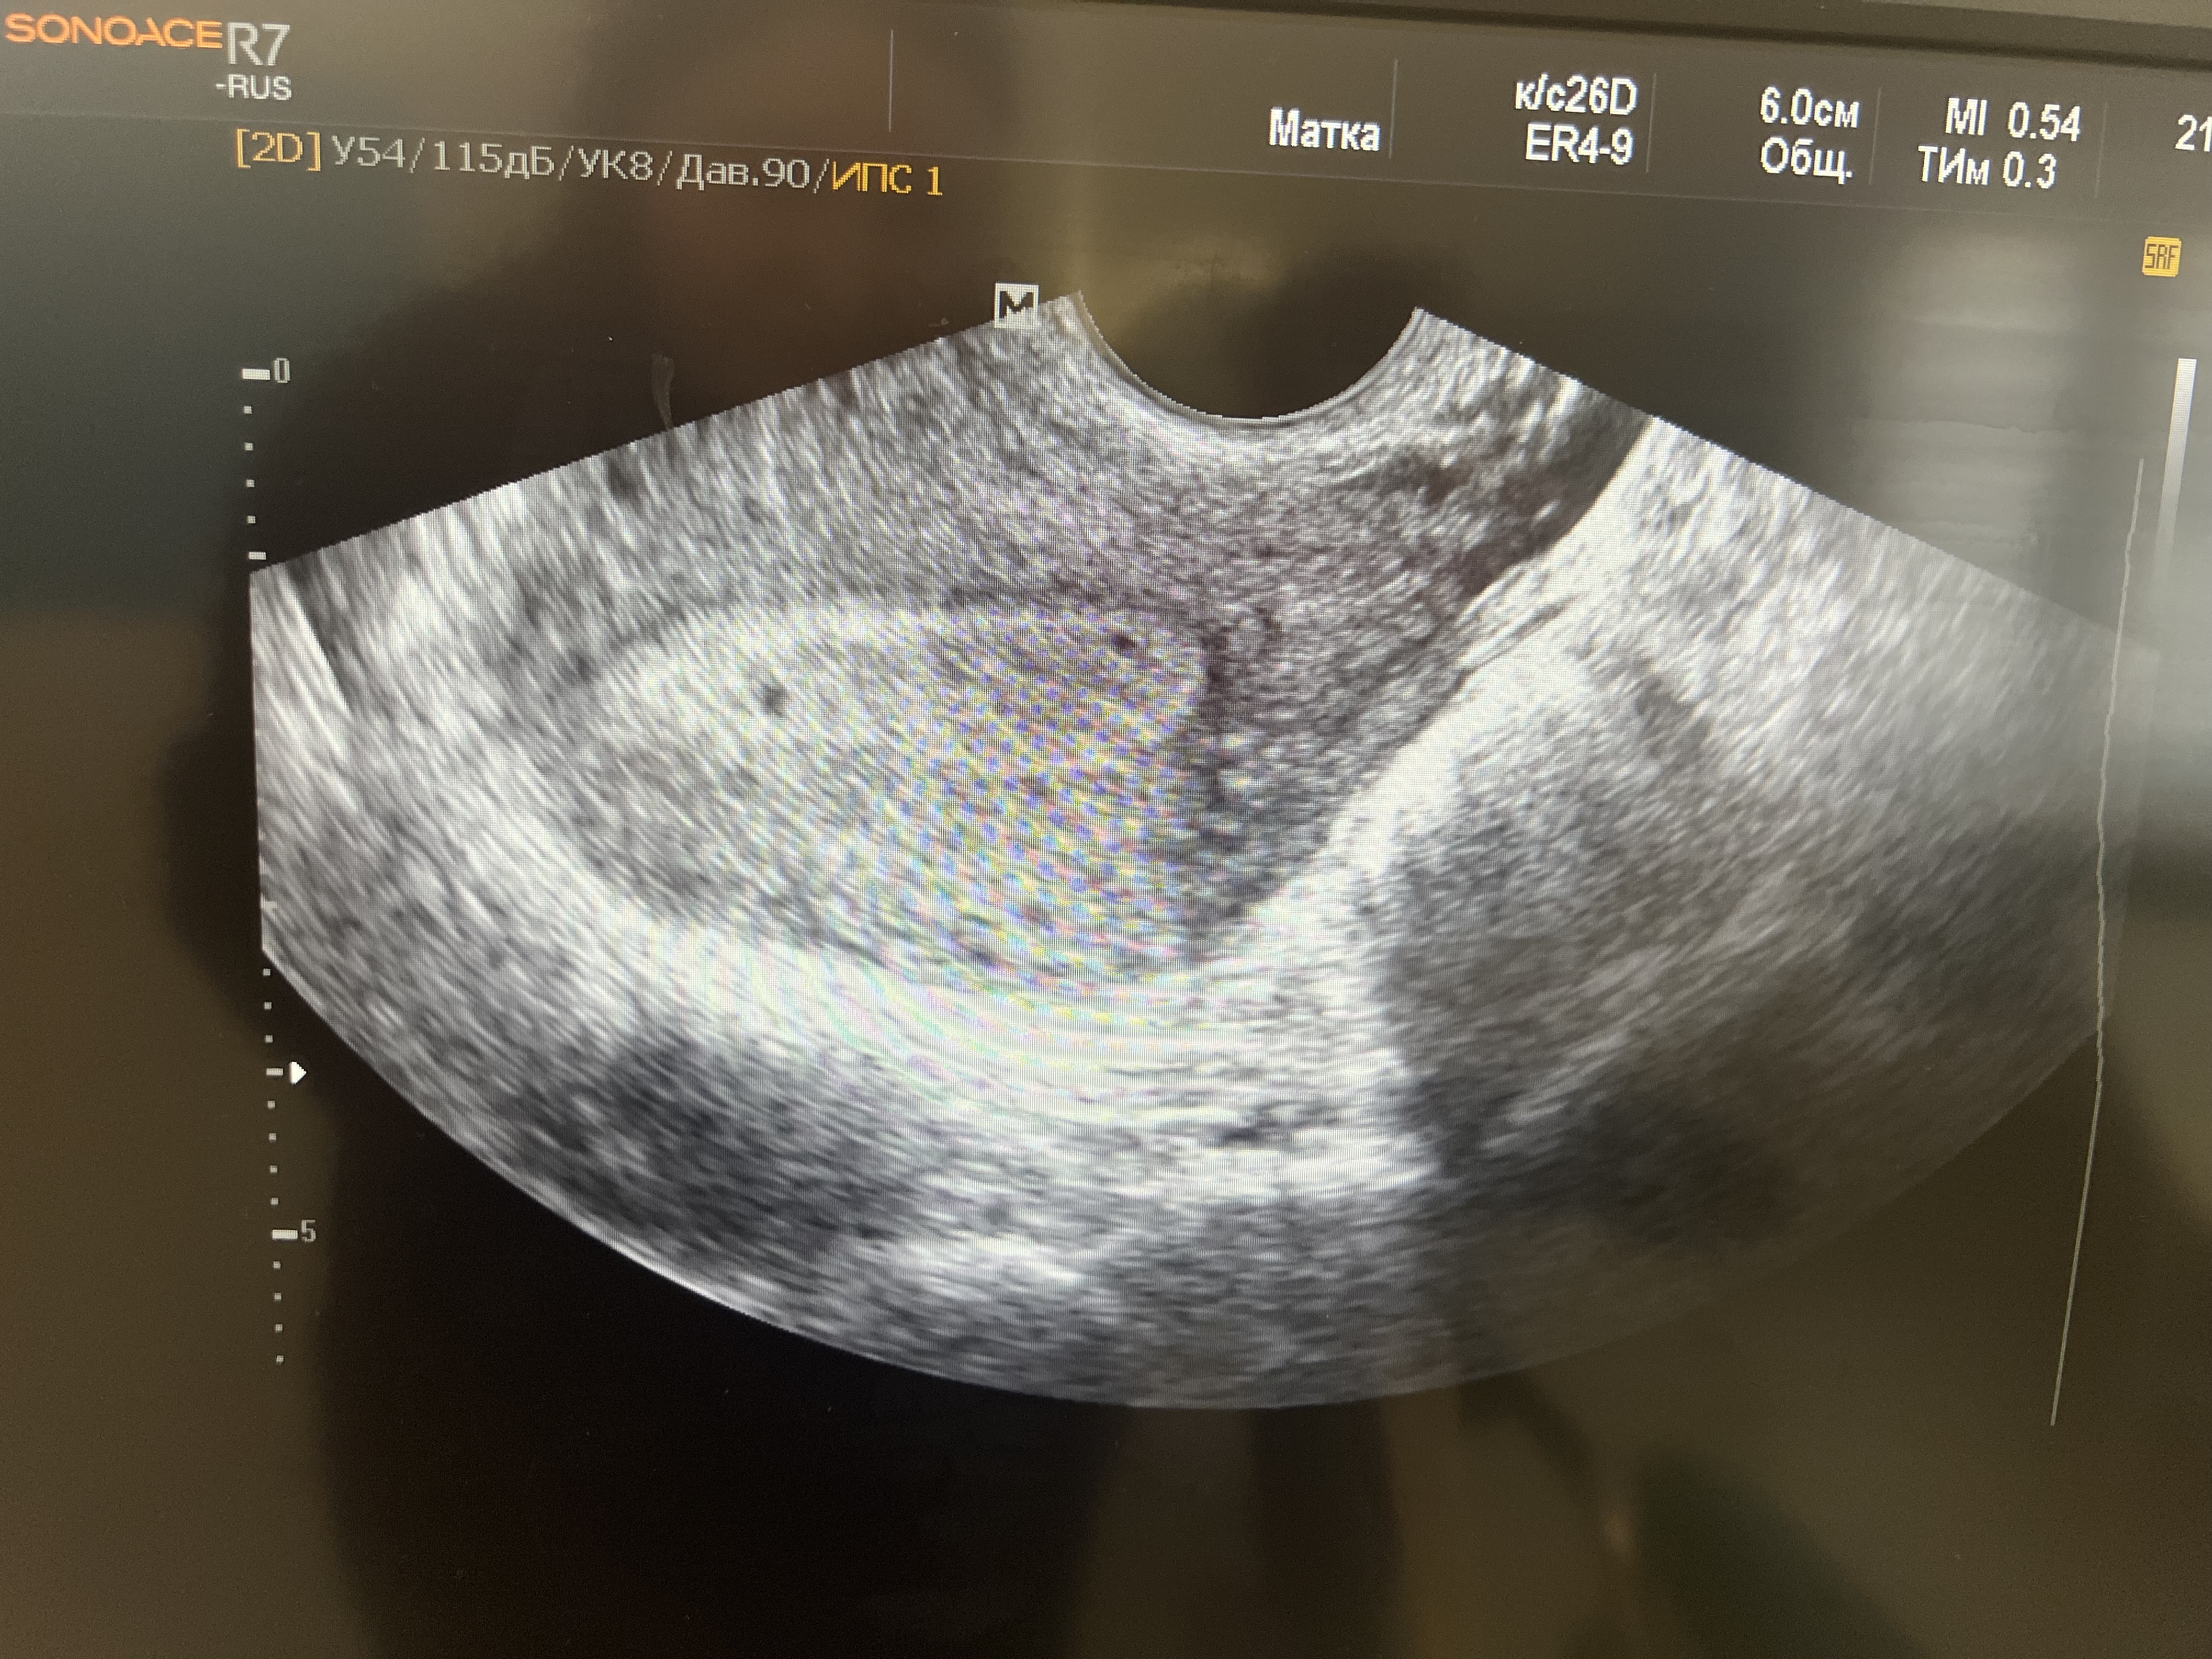

Явного плодного яйца здесь точно нет. Раз тест отрицательный, и беременности нет. Выдыхайте.

Tatiana, мы смотрели ближе, похоже на плодное яйцо.. даже на 2..

Екатерина Иголкина, точечки на экране не всегда означают плодное яйцо. Это могут быть банальные сплетения сосудиков. Сдайте ХГЧ. Если он меньше 5, это точно не беременность. Сначала показывает тест, потом появляется ПЯ. Иначе просто не бывает.

Ой, ерунду

Точки как у вас, у вас тут даже не 2, а 4 можно начитать